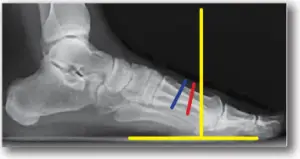

STEP 2: Create transverse osteotomy through the metatarsal using a saw.Angle the osteotomy towards the 5th metatarsal head while splitting the difference of perpendicular to the long axis ofthe metatarsaland perpendicular to weight bearing surface. Split the difference of perpendicular to the long axis of the metatarsal (blue line) and perpendicular to the ground (yellow lines). Red line is orientation of osteotomy.